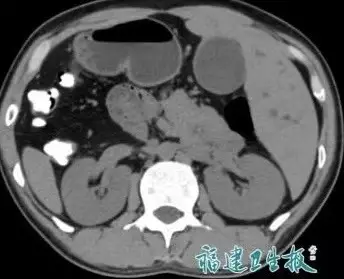

另外,陳先生還同時被發現患有膽總管結石,需接受手術治療。由於解剖結構極為特殊,部分醫療機構在評估風險後未敢接收,最終轉診至福建醫科大學吳孟超紀念醫院,由肝膽外科團隊接手。

「鏡像手術」精準取石 2小時完成高難度操作

為降低風險,團隊在術前進行周密準備,包括3D影像重建、膽道變異預判,以及多學科會診,為患者制定專屬麻醉及手術方案。最終,醫生採用腹腔鏡結合膽道鏡的方式,在「反向視野」下完成取石手術,全程約2小時,出血量不足50毫升,成功避免傳統手術需長期放置引流管的不適。患者術後恢復理想,一周後已康復出院。